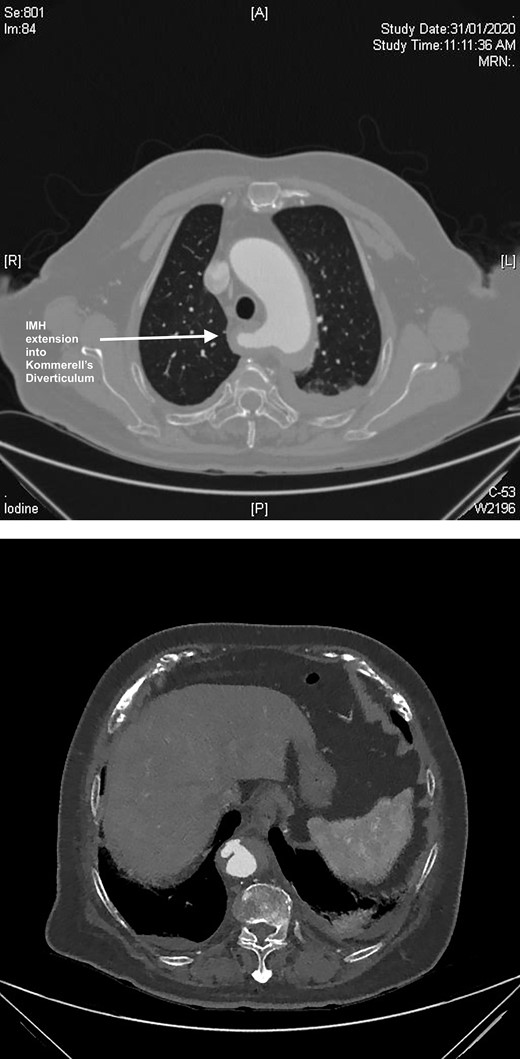

A semi-urgent endovascular thoracic aorta repair (TEVAR, Navion, Medtronic) was performed, with bilateral carotid–subclavian (C-S) bypasses. Intraoperatively, the IMH was noted have progressed to involve the usual mid-segment of the subclavian artery. As a result, a further bypass onto axillary artery was required. She made an uneventful recovery with follow-up imaging at 7 days and 1 month postoperatively showing slow resolution of her IMH and patent bypass grafts (Fig. 2A, B).

(A) 3D-CT reconstruction of extra-anatomical debranching of supra-aortic vessels with bilateral C-S bypasses. (B) 3D-CT reconstruction of thoracic endovascular repair.